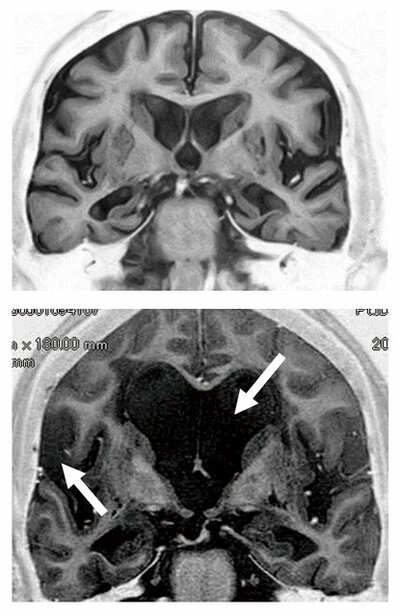

精神科医塩入俊樹氏前回お話しした「報酬系」の神経回路に関係する主な脳部位を示したものが図です。「報酬系」は、食行動や性行為などの本能的行動を快感として感じることで、生命を維持するためのこれらの行...